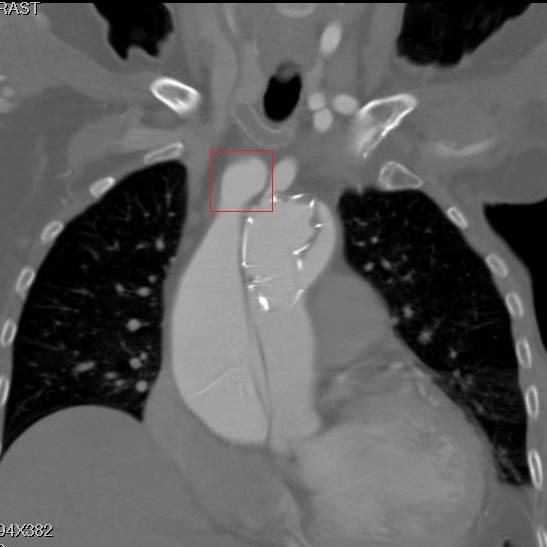

冠状面重建,方框示头臂干看上去完全开口于假腔,左颈总似乎被支架盖住了